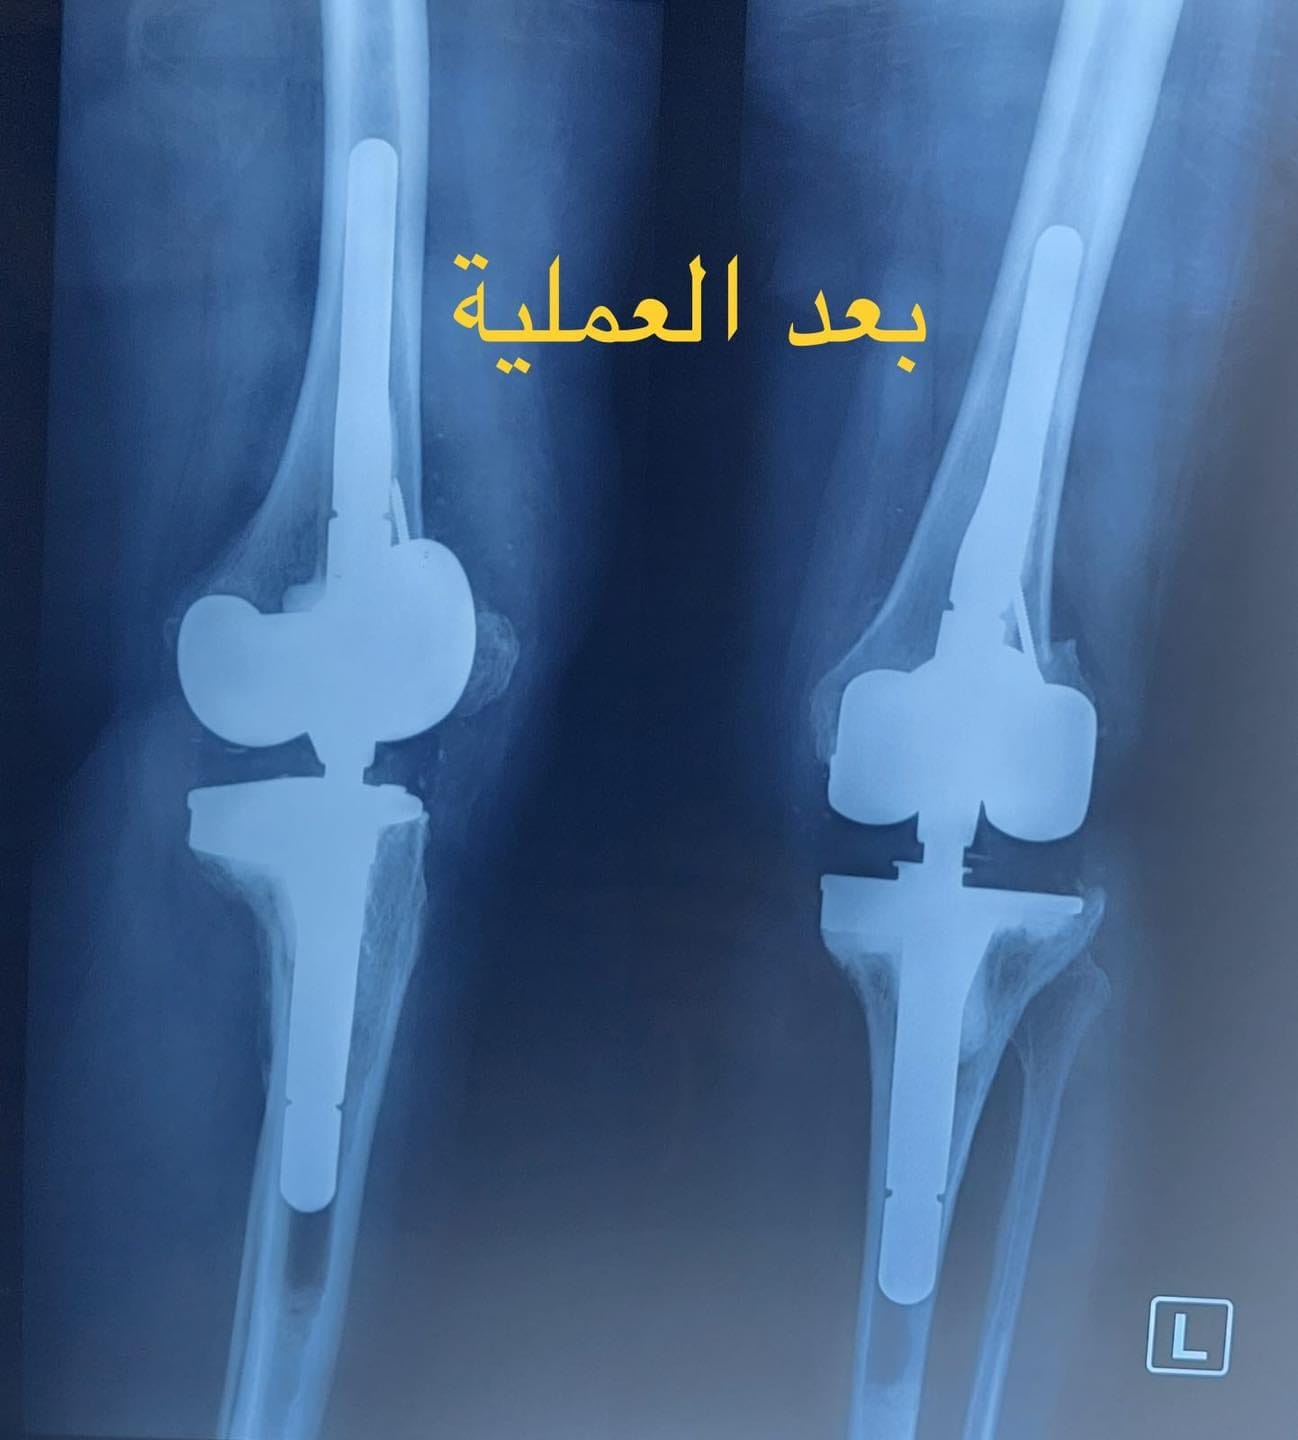

فريق طبي بمستشفى ابن سينا التدريبي في بغداد يجري عملية معقدة لمريضة بعمر (70) عام

تنفيذا لتوجيهات السيد وزير الصحة الدكتور صالح مهدي الحسناوي بتقديم افضل الخدمات الصحية للمرضى اجرى فريق طبي...